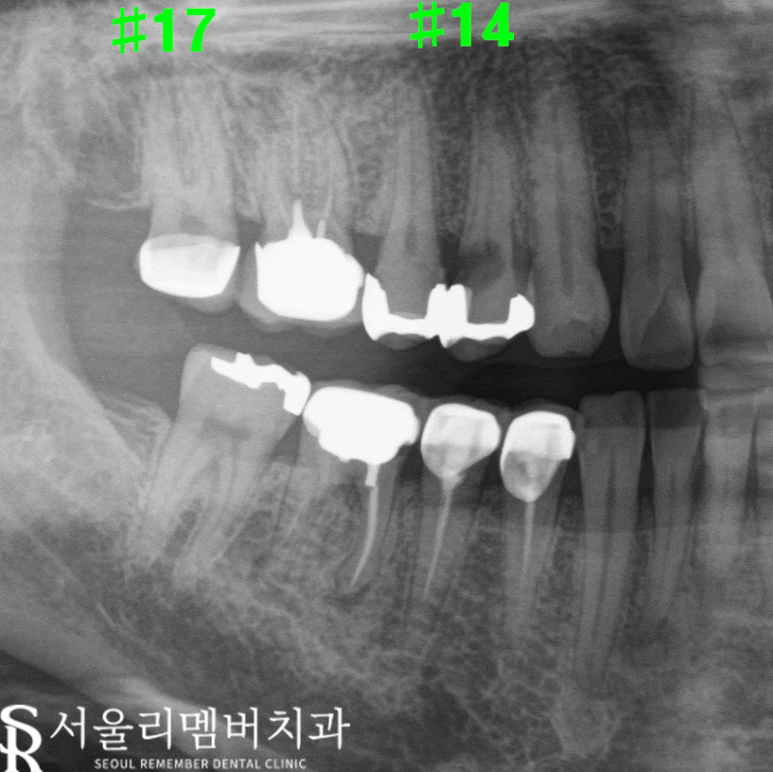

▶ #17:

기존에 있던 PFM 포세린 부분이 깨진 모습이었습니다.

이로 인해 이가 예민해질 수 있었습니다.

▶ #14:

인레이 하방으로 거뭇거뭇한 것이 보였습니다.

이는 치아 내부의 충치가 진행되었음을 의미하죠.

정확한 계획 단계

엑스레이를 통해 각 치아를 자세히

살펴본 결과는 다음과 같았습니다.

👉 #17:

기존 PFM 포세린 부분만 깨지고

치아 자체에는 큰 문제가 없어

지르코니아로 재보철을 계획했습니다.

지르코니아는 내구성이 강하고

자연스러운 외관을 자랑합니다.

👉 #14:

인레이 하방으로 우식이 치근 및 신경까지

심하게 진행된 상태로, 사당 치과 는

발치 후 임플란트를 계획했습니다.

우식이 진행되면 신경 치료가 필요할 수 있습니다.